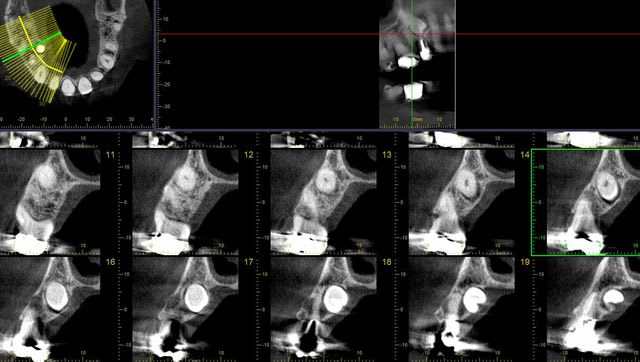

voici 2,3 coupes ...

dans ce cas, c'est différent...le cône beam nous donne toutes les informations nécessaires pour savoir si c'est réalisable ou non, et là oui, pour avoir tracté un certain nombre de dents incluses, il est quasi certain que la mise en place de cette 25 ne posait aucun problème...peut être même en seulement quelques mois...